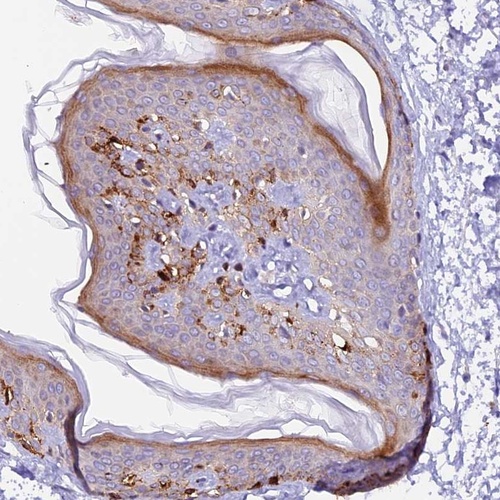

Immunohistochemical staining of human skin shows strong cytoplasmic positivity in subsets of cells.